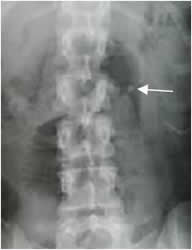

Fig 18. Litiasis.

Rx AP. Cálculo proyectado sobre la pelvis renal izquierda, que produce espasmo muscular y leve desviación dorsolumbar derecha.